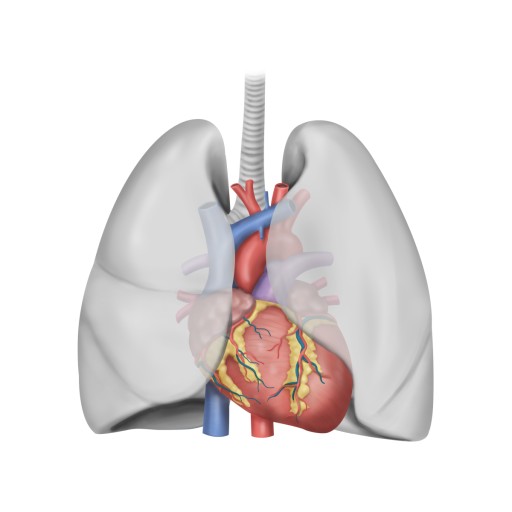

오늘은 정말 많은 분들이 놓치기 쉬운 **치명적인 심장 질환, ‘심근경색’**에 대해 이야기해보려 합니다.심근경색은 말 그대로 심장 근육이 괴사하는 질환으로, 골든타임을 놓치면 생명을 잃을 수 있는 응급상황입니다.